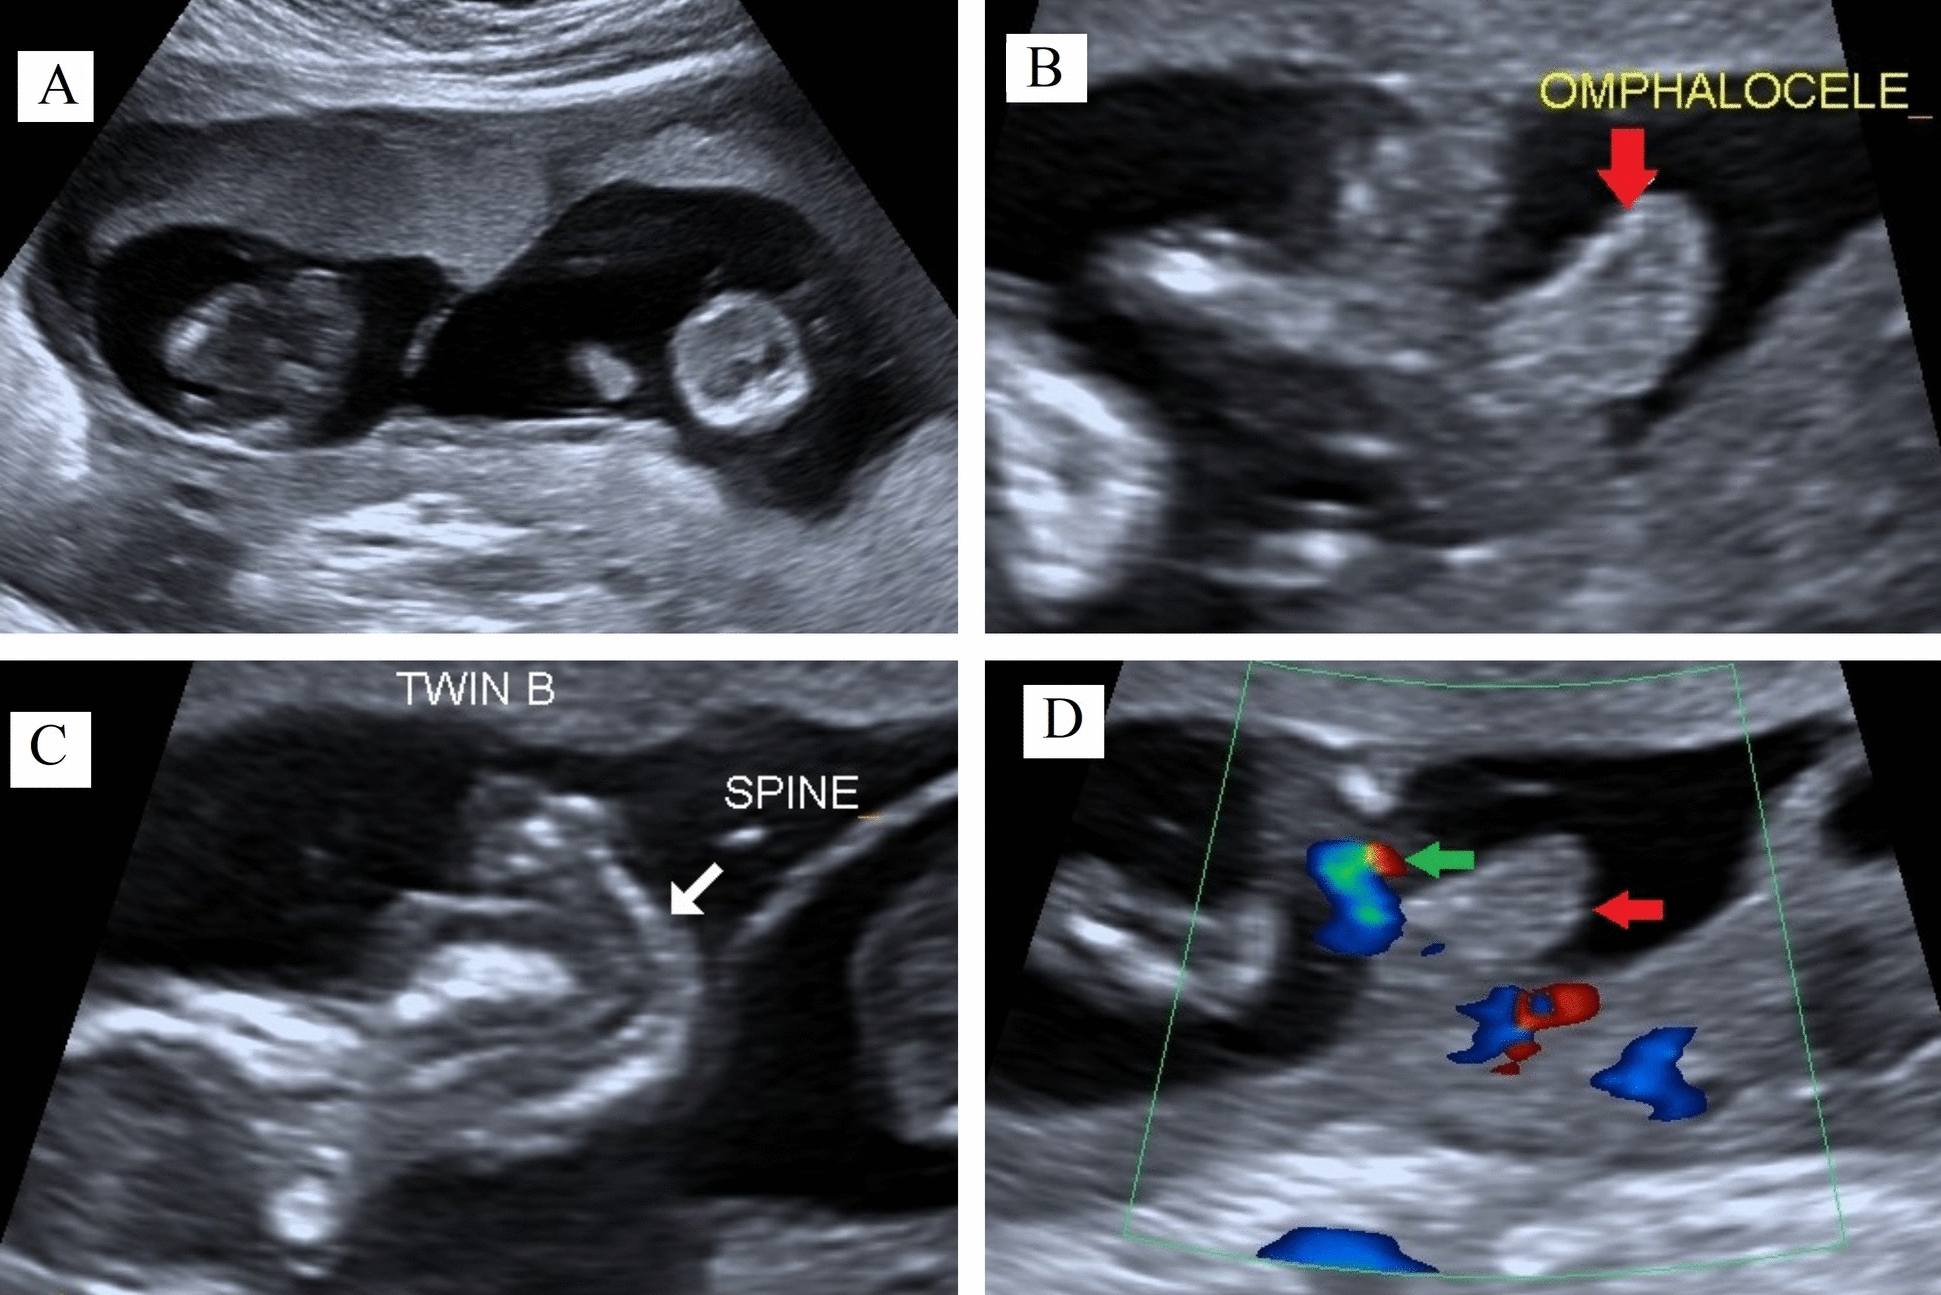

Case report: This report presents two cases: one of true omphalocele in a twin pregnancy and another of pseudo-omphalocele, underscoring the importance of careful assessment. The first case involves a twin pregnancy at 12 weeks' gestation, conceived through assisted reproductive technique in a 38-year-old Nepali woman of Indo-Aryan ethnicity. During a routine check-up, one twin was diagnosed with omphalocele. Trans-abdominal fetal reduction of the anomalous twin was performed. The other twin progressed to term and was delivered via cesarean section at 39 weeks. The second case involved pseudo-omphalocele, observed at 15 weeks' 3 days of gestation in a 32-year-old Nepali woman of Tibeto-Burmese ethnicity. Initially, the fetal abdomen appeared to herniate, mimicking omphalocele. However, a repeat examination after 30 min showed no herniation or defect. Retrospective analysis revealed that the misdiagnosis occurred because the fetal abdomen was compressed between the contracted myometrium and placenta.